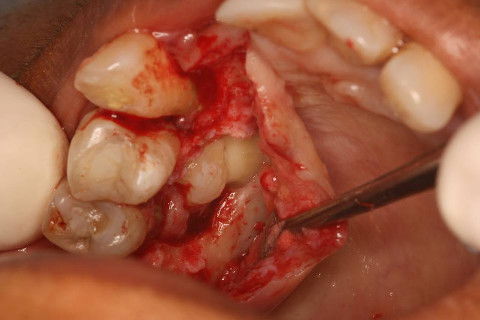

Osteotomia e Odontossecção(a coroa foi seccionada da raiz)

Loja Cirúrgica pós-extração